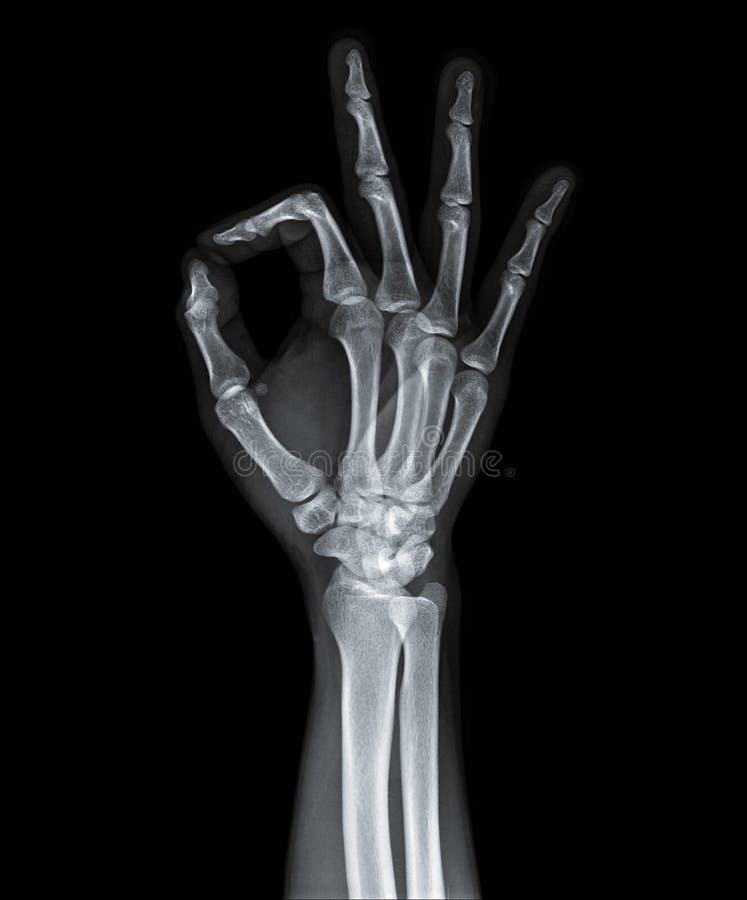

Fingers X-Ray . Fractures and dislocations are usually straightforward to identify, so long as the potentially injured bone is fully visible in 2 planes. Finger pa view is a standard projection for radiographic assessment of the fingers; It is one of three views of the finger. The hand comprises the metacarpal and phalangeal bones. Foreign body detection and localization. It uses a small amount of.